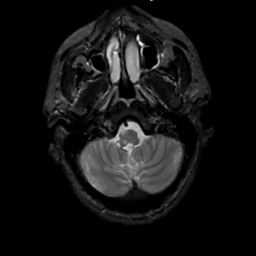

MR Study #1, February 10, 1991 -- Slice #7

[Home][Help][Clinical][Tour 1][Tour 2] Slice 7